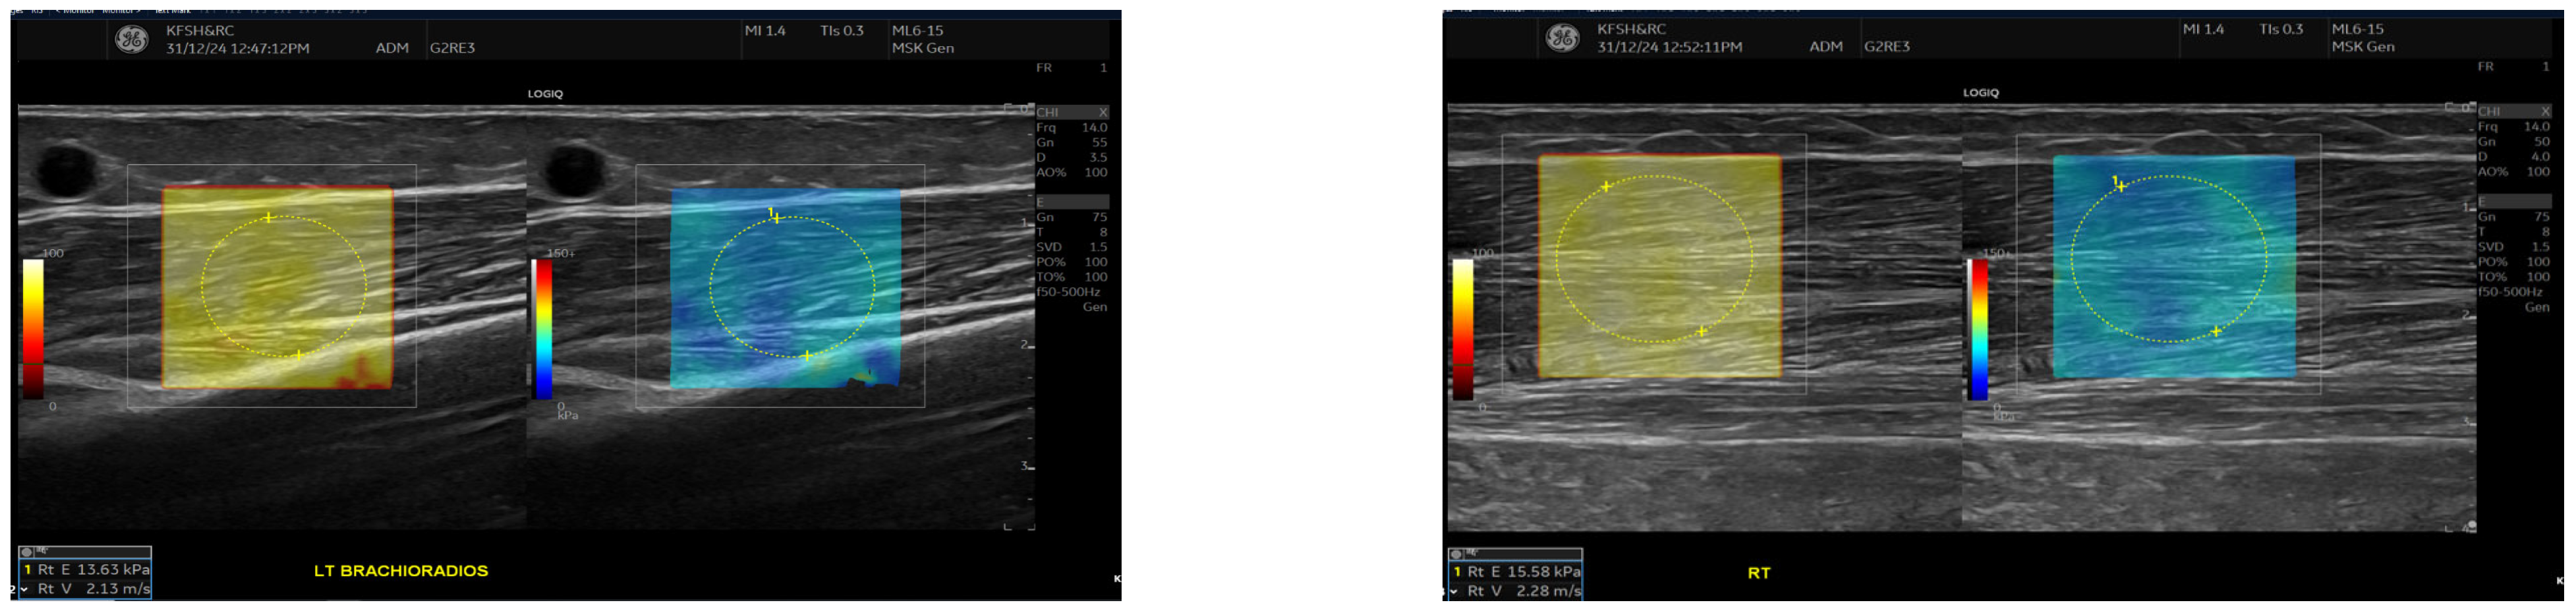

Figure 3.

This figure shows the comparison of brachioradialis muscle stiffness between the fistula and the contralateral arm. Shear wave elastography images showing stiffness measurements of the brachioradialis muscle. The left panel (fistula side) demonstrates a mean elasticity (velocity 2.13 m/s), while the contralateral arm (right panel) shows slightly higher stiffness (velocity 2.28 m/s). Measurements were taken in the mid-muscle belly using a high-frequency linear transducer, with Colour maps indicating relative stiffness (warmer colours represent higher stiffness).